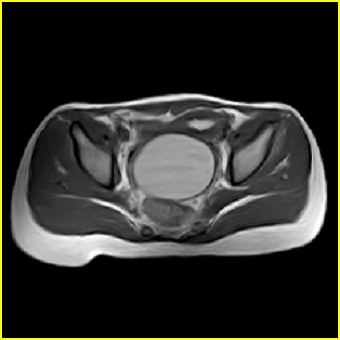

女、15岁、下腹疼痛2天,排尿困难1天。查体:处女膜闭锁,距处女膜约4至5cm处扪及一约5cm直径的圆形包块,张力较高,触痛明显、欠活动。b超提示子宫增大伴宫内增强回声团。

影像意见:子宫直肠陷凹积血。

更正影像意见:阴道积血。

处女膜闭锁,阴道积血

处女膜闭锁,阴道积血,子宫积血.

先天性处女膜闭锁,伴阴道积血,不除外先天性阴道粘液囊肿形成。

阴道积血,子宫积血.

子宫及阴道积血。

处女膜闭锁,伴子宫及阴道积血.